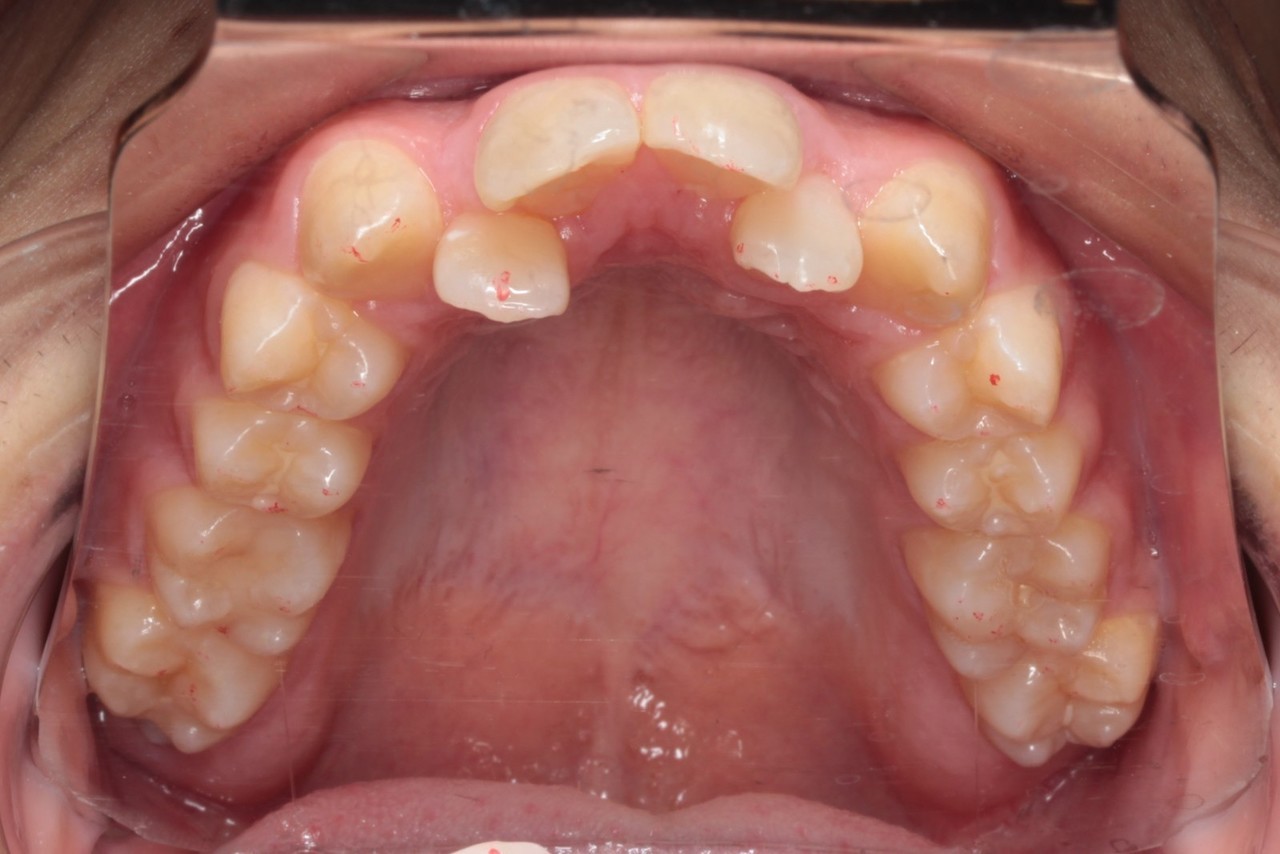

上顎 治療前

上顎 治療後

今回の症例は写真のように上の中心から2番目の歯が左右とも奥に入り込んでいてかなりスペースのない状態でした

にもかかわらず今回は非抜歯矯正での対応となります